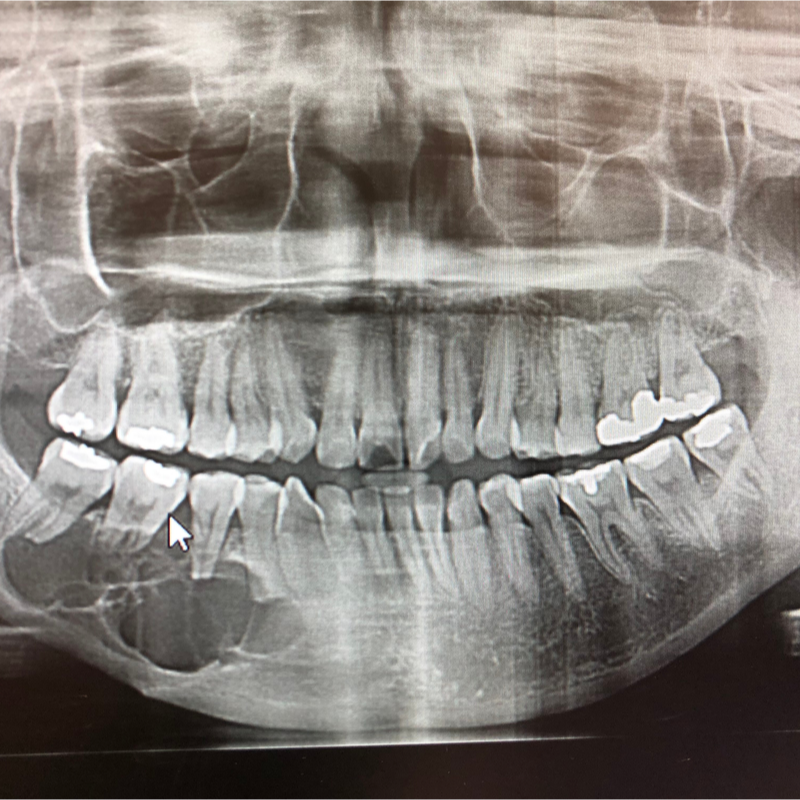

Поскольку одонтогенные опухоли обычно не вызывают никаких симптомов, их часто диагностируют как случайную находку, например, во время осмотра, . Одонтогенную опухоль можно визуализировать с помощью обычных процедур визуализации. Для постановки точного диагноза необходимо гистологическое исследование опухолевой ткани.